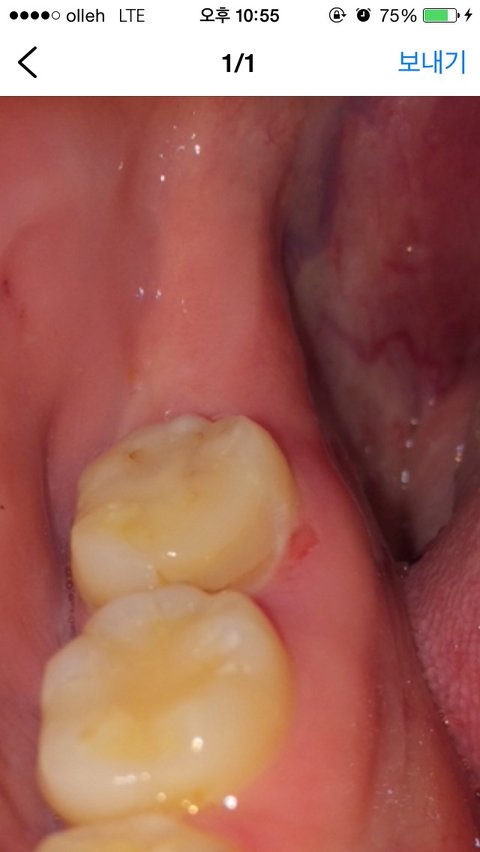

제가 치아 교정 중이었는데 어저께 교정장치를 치과에서 제거했는데 장치를 떼더니 오른쪽 아래 끝 어금니 안 시렸냐며 깨져있다고 하시더군요 치아가 깨졌다는 게 아니고 전에 충치치료하고 때운 부분이 떨어져 나가있다고 하면서 유지 장치 착용 전의 이거를 씌우고 왼쪽 아래 끝 어금니도 충치치료를 해야 한다며 전체 씌우는 거 40만 원 부분 채우는 거 32만 원이라고 하더군요 근데 너무 비싼 거 같아서 비싸다니까 68만 원까지 깎아주겠다고 하더라고요 근데 아무리 생각해도 비싸고 찜찜해서 다른 병원에서 치료하고 여기선 교정만 하겠다 하고 돌아왔는데 잇몸에 상처가 난 거 같아서 거울을 보니까 이가 깨져있고 잇몸에 상처도 나있었어요

이렇게 티가 나게 깨져있는데 제가 치과 바로 가기 전에도 양치하고 치 실질 했을 때도 이러지 않았는데 저 어금니 안쪽에 브래킷 장착했었고요 아무래도 브래킷 제거하면서 깨진 거 같은 느낌이 들더라고요 그래서 오늘 충치 검사할 겸 다른 치과 갔는데 저거 깨진 거는 치아 때운 게 깨진 게 아니라 제 치아가 깨진 거고 32만 원 주고 부분만 씌우라고 했던 왼쪽 아래 끝 어금니는 겉에 충치는 있지만 씌울 필요는 없고 주기적으로 검사는 하되 더 심해지면 씌워야 한다고 하더라고요 바로 교정치과 전화해서 어제 마지막 상담한 실정한테 이때 운 게 깨진 게 아니라 제 치아가 깨졌는데 뭔 말이냐니까 깨졌다는 말은 한 적이 없고 충치가 심해서 씌우라는 거였다고 그래서 내가 방금 다른 치과를 다녀왔는데 깨지기만 했지충치는 아예 없다고 하고 그쪽에서 치료하라는 반대편 치아는 치료할 필요 없다고 했다 장치 떼면서 그쪽에서 깨트려놓고 왜 나한테 돈 내라고 하냐 했더니 치과에 오라고 해서 가겠다고 하고 혹시나 사진 조작할까 봐 처음 사진 보고 어느 쪽 치아든 육안으로 깨진 치아가 있느냐라고 했더니 없다고 하더라고요 치과에 가서 실장을 만났는데 원래 오른쪽 맨 끝 치아는 깨져있었다며 말을 또 바꾸길래 아까없다하지않았냐니까 치아 겉 쪽만 확인했지 안쪽을 확인 못 했다 하길래 내 치아가 처음부터 깨져있었으면 지금 사진 찍어 비교했을 때 같아야 하는 건데 내가 모르고 있었다면 지금 사진 찍어서 비교를 하자니까 눈에 띄게 깨져있더라고요

이게 처음 사진이고

이게 지금 사진인데 어떻게 같을 수 있답니까

누가 봐도 티 나게 깨져있는데 ..

이게 지금 같아 보이느냐 원래 깨져있었으면 장치

치료하기 전에 이걸 치료를 하고 했었어야 하는 거고 어제 장치를 제거하면서 깨진 게 아니라 그전에 깨져있었다면 내가 2주 전에도 왔는데